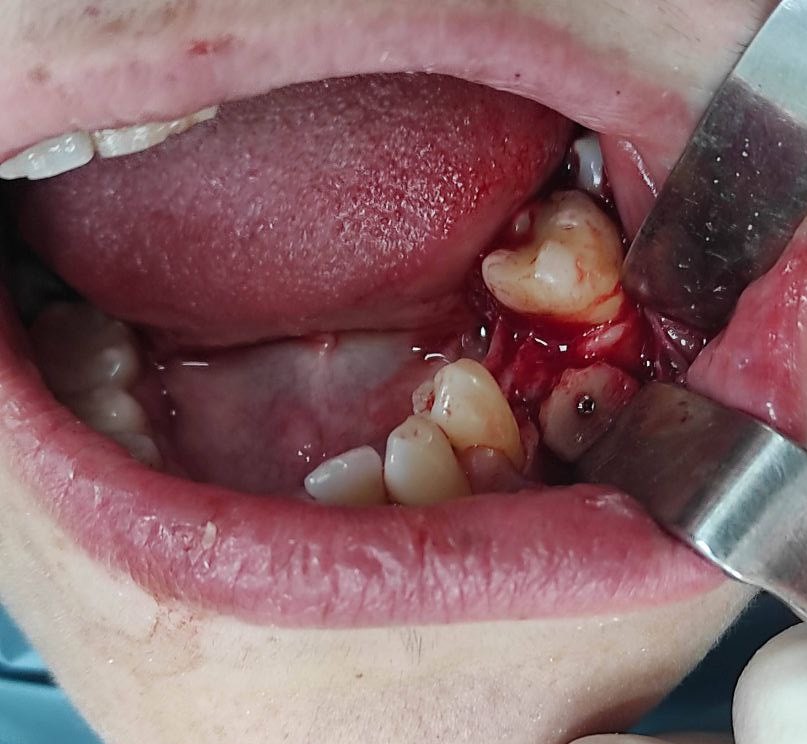

Los implantes dentales son una solución avanzada para la pérdida de piezas dentales. Este procedimiento consiste en la colocación de una raíz artificial de titanio en el hueso maxilar, sobre la cual se instala una corona dental personalizada que imita a la perfección la forma y color del diente original. Este tratamiento es ideal para restaurar incisivos superiores, devolviendo la funcionalidad y estética de la sonrisa de manera natural y duradera.

4.1 – Implante dental de incisivo superior